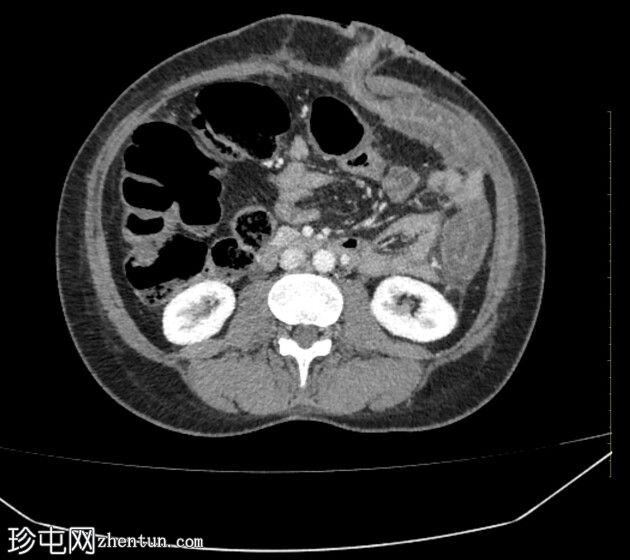

CT

轴位增强扫描(C+)门静脉期

正位片

这张有限的代表性轴位CT图像显示存在持续性结肠炎。